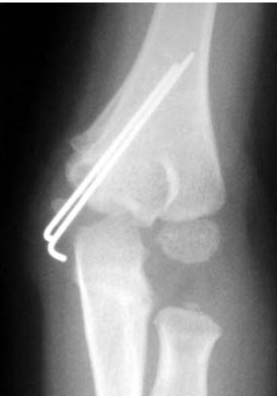

Patient Data

Fx: Fracture, Dx: Diagnosis, MCF: Medial condyle fracture, MRI: Magnetic resonance imaging, Intraop.: Intraoperative, OR/IF: Open reduction and internal fixation, LOM: Limitation of motion, ROM: Range of motion.